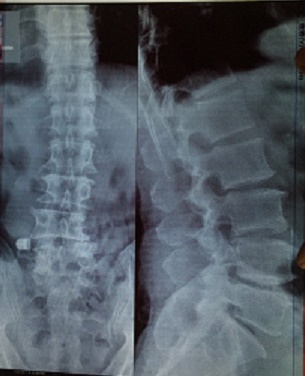

二零一七年四月二十六日,这个邻居腿腰痛的受不了了,就去医院,结果医生拍的片子是脊骨下五段不直了,骨头增生,右大腿钻轴不圆了。邢台治不了,得去北京军医院手术。

'邻居脊骨下五段片'

邻居脊骨下五段片